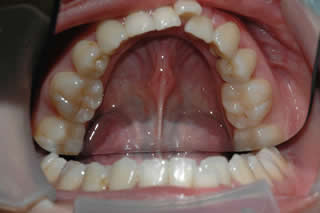

Lower Incisor Crowding:

Late lower incisor crowding is a very common problem.

3 - 9 months of treatment can correct the mild-moderate lower incisor crowding.